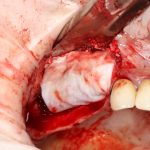

Синуслифтинг с одномоментным удалением зуба (и одномоментной имплантацией, если таковая потребуется).

Еще проще. Разрез начинаете от экватора соседних зубов, по такому же принципу, как и в предыдущем пункте. Если адекватный разрез для синуслифтинга мешает сделать коронка зуба или её остатки — спилите их нафиг перед началом работы. Заранее сделанные разрез и скелетирование помогут вам аккуратно удалить зуб. Далее, скелетируетесь примерно на 10 см выше проекции щечных корней и вперед, делать дырку в полость: